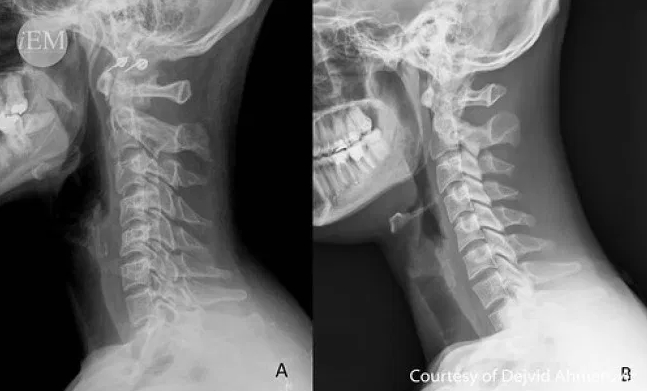

목디스크는 경추 뼈와 뼈 사이에 있는 물렁뼈 조직인 디스크가 어떠한 원인에 의해 탈출하여 신경을 눌러 통증을 일으키는 질환입니다. 일반적으로 목디스크는 퇴행성 변화에 의해 수핵의 탄력성이 떨어지면서 발생하는 경우가 많지만 최근에는 일상생활에서의 잘못된 자세습관에 의한 변형(거북목, 일자목), 운동 중 부상 등으로 발생하는 경우가 많습니다.

목디스크 증상

- 초기 증상 : 목이 뻐근하고 결리는 통증 및 움직임 제한 등이 있습니다.

- 중기 증상 : 디스크 탈출이 가속화되어 신경을 누르게 되며, 목 뿐 아니라 어깨, 팔, 손까지 저리고 아픈 통증을 겪게 됩니다.

- 말기 증상 : 목덜미가 뻣뻣해지는 느낌과 더불어 두통, 어깨 저림, 팔 저림 등이 나타나게 되며 이는 원만한 일상생활을 더욱 방해하는 요인이 됩니다.